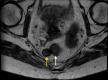

Figure 10

Figure 10. Axial MRI demonstrating a right perirectal T2 heterogeneous mass (yellow arrow) measuring 1.6 x 1.5 cm with T2 hypointense signal and T2 intermediate signal intensity with mild diffusion restriction and heterogeneous enhancement. The mass involves the right lateral rectal wall (white arrow).

MRI: magnetic resonance imaging